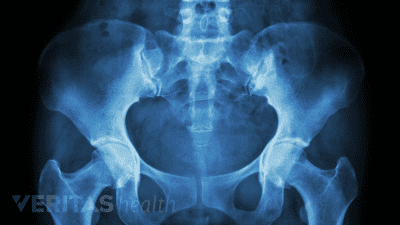

Discover the best radiographic tests for diagnosing SI joint dysfunction and ruling out serious medical conditions.